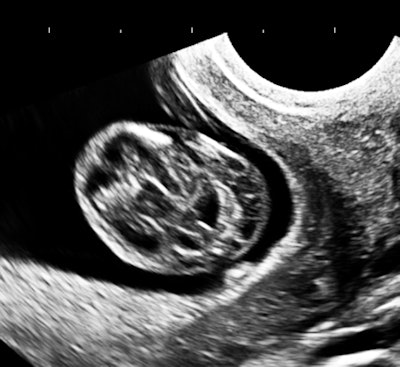

Case 1: Pregnancy, day 64

My own private practice has some routine scanning from local physicians and second-opinion scanning from a much wider geographic zone. Most of the "abnormal NT" cases I used to see were just normal embryos resting supine on the amnion. A recent case was referred from an infertility practice: an 11.2-week embryo thought to have an abnormal NT. This embryo, having a higher specific gravity than amniotic fluid, was dependent in the sac, resting on amnion. Here are an endovaginal view of the neck, an energy Doppler view of the heart, and a 3D survey:

There are multiple cystic hygromas and an apparently normal heart. The 3D really does not look "right" because of a disproportion. No other abnormal findings were evident. We did a cell-free fetal DNA test on maternal blood that established in a few days that this is a case of Trisomy 18.